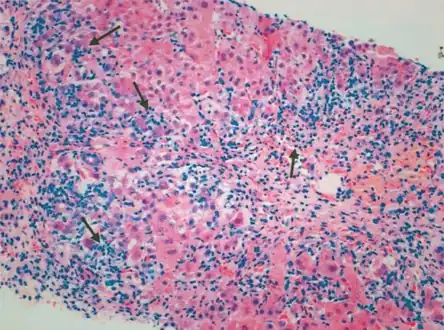

Giant cell transformation in autoimmune hepatitis -

Portal and periportal inflammatory infiltrate- interface hepatitis (piecemeal necrosis) arrow(s)